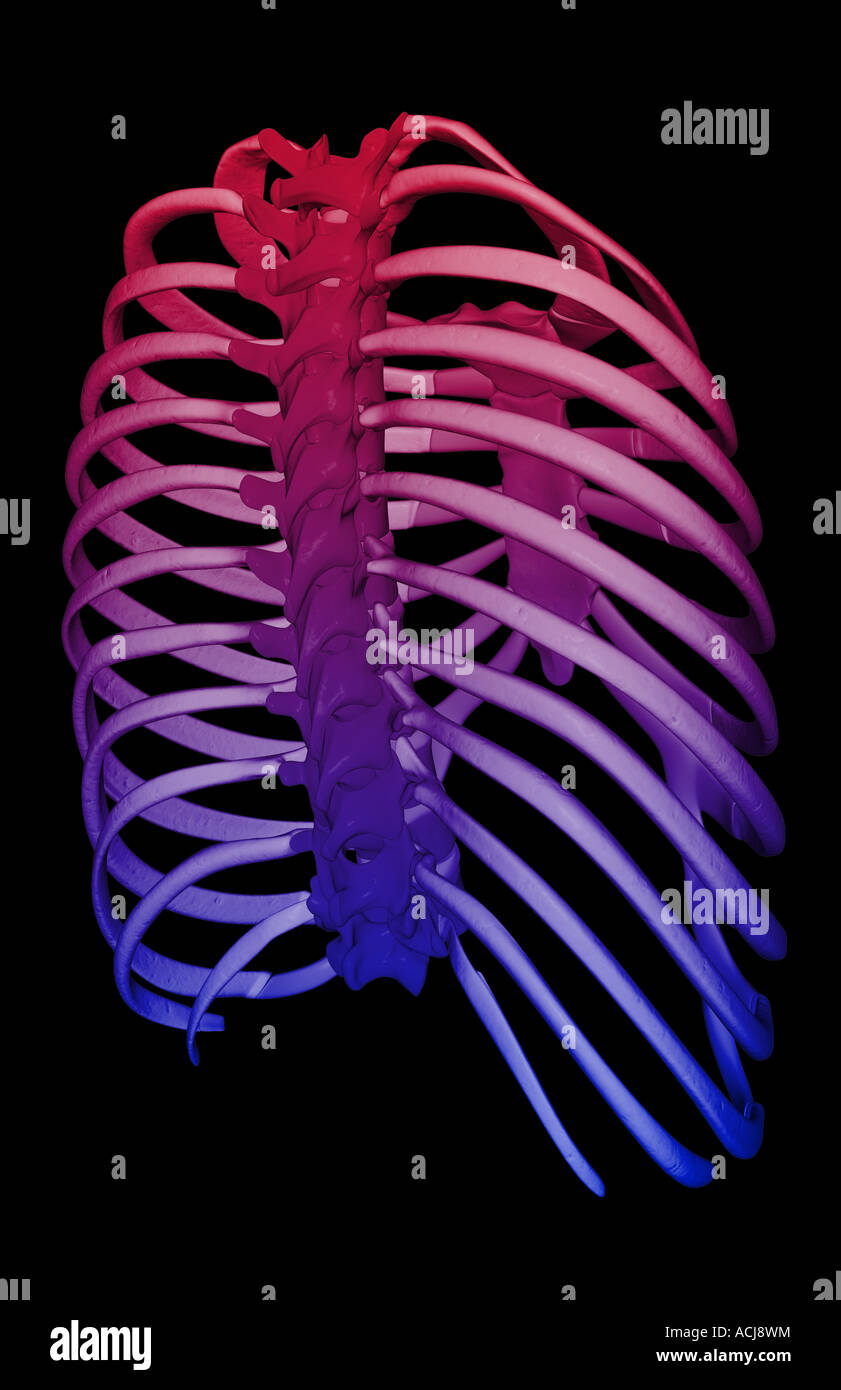

RMPFM8F8–Una guida completa all'anatomia e alla fisiologia, che descrive dettagliatamente la struttura del torace e le variazioni nella formazione delle costole, comprese le costole sovrannumerarie e la presenza di processi trasversali. Il lavoro esplora l'analogia tra processi trasversali e costole, evidenziando le variazioni anatomiche negli esseri umani e negli animali.

RMW24GKR–Immagine di archivio da pagina 240 della encyclopaedia - Wikizionario di anatomia e. Il encyclopaedia - Wikizionario di anatomia e fisiologia cyclopdiaofana0402todd Anno: 1849 TORACE. 1025 di una coppia di cervicale o lombare nervature: in questo caso le nervature in soprannumero sono formate dalle parti anteriori dei processi trasversali né della settima vertebra cervicale o prima vertebra lombare ; che permette di ottenere una forte prova dell'analogia esistente tra un processo trasversale e una nervatura. A volte il numero abituale è diminuito a 22 : questo è più raramente il caso. Quando questo si verifica, talvolta troviamo due nervature adiacenti uniti in tutta la loro ent

RMMA77DE–. Elementari di anatomia e fisiologia : Per college, accademie e altre scuole . Una vista anteriore dei legamenti delle vertebre e delle costole. 1, la sezione anteriore del legamento vertebrale. 2, il costo anteriore- legamento vertebrale. 3, l'interno legamento trasversale. 4, il Inter-Ar- o sovracapacità per particolari legamento, colleganti la testa della costola al sub intervertebrale- posizione. Una vista dell'articolazione della mandibola, dato dalla segatura attraverso il giunto. 1, la Fossa glenoide. 2, il tubercolo per condilo nel suo avanzamento- zioni. 3, la cartilagine Inter-Articular. 4, il superiore della cavità sinoviali. 5, il file INF

RMW9G8YY–Immagine di archivio da pagina 144 di Cunningham il libro di testo di anatomia (1914). Cunningham il libro di testo di anatomia cunninghamstextb00cunn Anno: 1914 ( le nervature. Ill sfaccettature sulla testa Xeck Xon-articolare parte del tubercolo parte articolare del tubercolo per processi trasversali delle vertebre Fig. 124.-quinta costola destra come visto da dietro. attrezzatura per esterni ed interni dei muscoli intercostali rispettivamente. Sul pavimento della scanalatura può essere visto anche le aperture dei canali per la trasmissione delle navi di nutrienti che sono orientati verso la estremità vertebrale della nervatura. La sezione anteriore o extremi sternale

RMPFYCG2–. Cunningham il libro di testo di anatomia. Anatomia. Parte articolare del tubercolo per processi trasversali delle vertebre Fig. 124.-quinta costola destra come visto da dietro. attrezzatura per esterni ed interni dei muscoli intercostali rispettivamente. Sul pavimento della scanalatura può essere visto anche le aperture dei canali per la trasmissione delle navi di nutrienti che sono orientati verso la estremità vertebrale della nervatura. La sezione anteriore o estremità sternale dell'albero, spesso leggermente ingrandita, visualizza un ovale allungata buca in cui la cartilagine costale è affondato. Nervature peculiare.-Il primo, il secondo, decimo e undicesimo di

RMPFYCG4–. Cunningham il libro di testo di anatomia. Anatomia. Le nervature. Ill sfaccettature sulla testa Xeck Xon-articolare parte del tubercolo. Parte articolare del tubercolo per processi trasversali delle vertebre Fig. 124.-quinta costola destra come visto da dietro. attrezzatura per esterni ed interni dei muscoli intercostali rispettivamente. Sul pavimento della scanalatura può essere visto anche le aperture dei canali per la trasmissione delle navi di nutrienti che sono orientati verso la estremità vertebrale della nervatura. La sezione anteriore o estremità sternale dell'albero, spesso leggermente ingrandita, visualizza un ovale allungata abisso nel quale le carti costiera